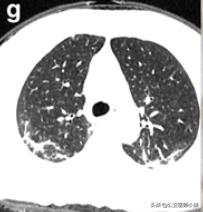

肺部感染涉及多个肺叶-1

肺部感染涉及多个肺叶-2

肺部感染涉及多个肺叶-3

根据感染的不同程度累积一个或多个肺叶